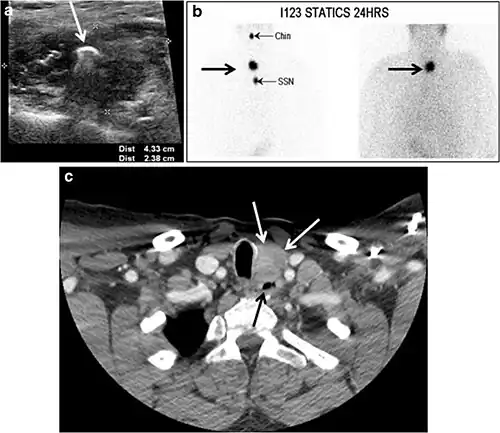

The likelihood of positive anatomic imaging is greater when serum Tg is >10 ng/mL. A diagnostic CT scan adds additional value to neck US in detecting central compartment macro-metastases in the mediastinum and retro-tracheal area. According to the recent American Thyroid Association guidelines, an upper chest and neck CT scan with IV contrast should be obtained when: 1) neck US is inadequate in visualizing possible local nodal disease (high Tg, negative neck US, and RAI imaging); 2) US is not able to delineate the disease completely, as in the case of bulky recurrent nodal disease; or 3) evaluation of possible recurrent invasive disease is needed (Figs. 7, 88 and and9).9). CT scans are also the most sensitive diagnostic tool for the detection of pulmonary micro-metastases. Many of the neck US features that are considered as suggestive signs of disease recurrence are also applicable to CT examination. These signs might include sizable rounded nodules in the thyroid bed, fine calcifications, or cystic change.[1]

Fig. 7. A 51-year-old female patient post total thyroidectomy for PTC with elevated thyroglobulin measurement. an Axial non-enhanced CT scan of the neck at the level of the thyroid bed demonstrates a well-defined, rounded, homogenously dense soft tissue situated between the trachea and left internal jugular vein (white arrow). b Transverse ultrasound image of the neck demonstrates a well-defined, homogeneous, hypoechoic soft tissue nodule measuring 6 mm (white arrow) with no detected micro-calcifications. Biopsy showed a predominantly residual normal thyroid tissue with micro-foci of PTC.[1] -

Fig. 8. A 48-year-old male patient post total thyroidectomy with PTC recurrence. a Transverse greyscale ultrasound of the neck demonstrates a left thyroid bed heterogeneous, predominantly hypoechoic irregular lesion with calcifications (white arrow). b A spot image of iodine 123 total body scan of the neck demonstrate a focus of abnormal radiotracer uptake at the left thyroid bed (Black arrows) between the annotated markers. c Enhanced axial CT scan of the neck demonstrates an enhancing large left thyroid bed mass (white arrow) with no calcifications. The lesion exerts a mass effect on the oesophagus (black arrow) and is inseparable from the trachea.[1] -

Fig. 9. A 58-year-old male patient with persistence PTC at thyroid bed with hypervascular nodal metastasis. a–c Transverse greyscale and colour Doppler neck ultrasound demonstrate hypoehoic soft tissue in the left thyroid bed (white arrow in a). There are a heterogeneous enlarged lymph nodes at level 2 and 3 with markedly increased vascularity (white arrow in b and c). d–f Enhanced axial CT images of the neck demonstrate a 2.7 × 1.4 cm hypodense soft tissue lesion anterior to the left carotid sheath (white arrow). There are left-sided enhancing abnormal and enlarged lymph nodes at cervical level 2 and 3 (black arrows).[1]